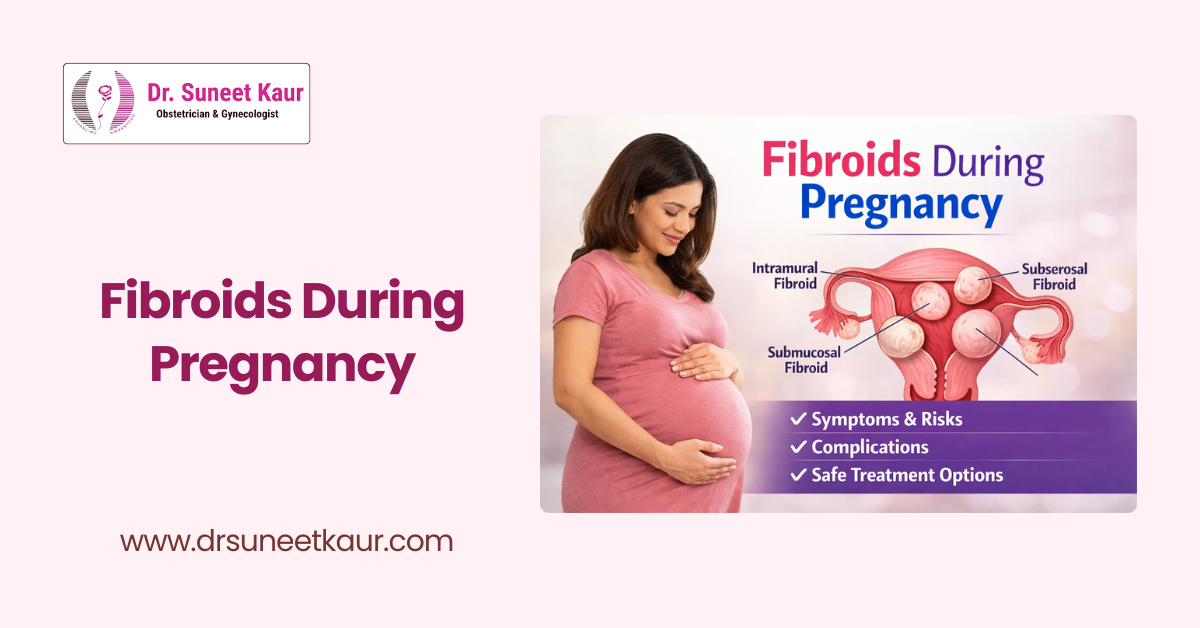

Uterine Fibroids

Non-invasive and surgical treatment options for fibroids causing heavy bleeding, pain, infertility, or pressure symptoms.

- Fibroid Uterus Treatment

Minimally invasive solutions for fibroids, ovarian cysts, ectopic pregnancy, and hysterectomy with faster healing.

Our Blogs

Comprehensive Care for Every Stage of a Woman’s Health

Advanced and compassionate care in Obstetrics, Gynecology, Infertility, and Robotic Surgery – all under one expert you can trust.